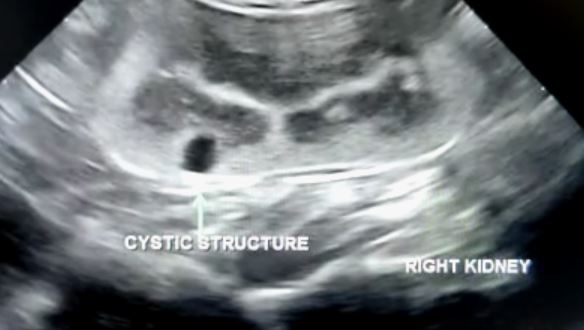

Ginger’s gallbladder is okay. The size of his kidneys are fine too. However, the vet detected a cyst in his right kidney.

It is a 4mm cyst.

How the cyst could have been formed is all by chance. It’s one of those things in life. The good thing about it is that the vet did not detect any blood vessel going to the cyst. But it still needs to be monitored for further growth or more cysts. Hopefully none of that will happen. Otherwise, it would be a whole new deal of management similar to what is required for a CKD cat. The cyst cannot be removed because that would involve cutting into the kidney which would cause even more damage. The vet advised that a blood test be done to check Ginger’s kidney readings.